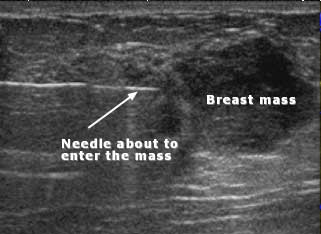

Ultrasound-guided biopsy of a solid breast mass shows biopsy needle about to enter the mass.

Note: Images are shown for illustrative purposes. Do not attempt to draw conclusions or make diagnoses by comparing these images to other medical images, particularly your own. Only qualified physicians should interpret images; the radiologist is the physician expert trained in medical imaging.